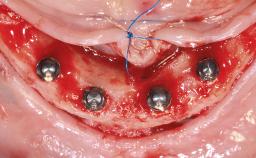

Simultaneous Maxillary and Mandibular Full-Arch Fixed Rehabilitation: Extractions, Immediate Implant Placement and Loading, and Definitive Zirconia Prostheses

| Timing of placement | Immediate Placement (extraction sockets) (Type I) |

| Number of implants | > Three |

| Available apical bone to achieve primary stability | Sufficient height ( ≥ 4 mm) and width (> 2 mm around apex of planned implant) |

| Socket walls | Partially missing. Extractions that result in small residual defects. Roots without associated bone defects |

| Thickness of buccal wall | 2mm or greater |

| Anticipated residual defect after implant placement | 2 mm or less |